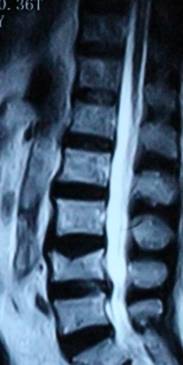

1.患者邹某,男,79岁,因“腰痛双下肢疼痛1年余,加重并间歇性跛行2月”于2014年3月26日入院。入院见患者腰痛病双下肢疼痛、麻木,间歇性跛行,行走约10余米,休息后略缓解。查:直腿抬高试验左40°(+),右55°(+),加强试验(+),腰背伸试验阳性。双侧膝腱未引出,跟腱反射减弱,双侧踇背伸肌力Ⅳ级。入院后诊断为腰椎管狭窄症。患者既往患糖尿病、高血压、冠心病病史。入院后完善检查,明确诊断,请相关科室会诊后认为手术风险极大。经科室讨论后行经皮椎间孔镜下髓核摘除并椎管扩大成形术,手术麻醉方式为局麻。于2014年3月29日行手术治疗,经椎间孔入路椎间孔镜下髓核摘除椎管扩大成形术。手术顺利,术中无出血,手术时间约40min。术中可与患者交流。术后患者即可感双下肢无疼痛,第二天佩戴腰围下地活动后双下肢无不适。术后半年复查腰椎MRI示突出髓核已摘除,神经根无受压。术后随访1年,患者目前病情恢复良好,无下肢疼痛、麻木,无间歇性跛行。

术后半年MRI